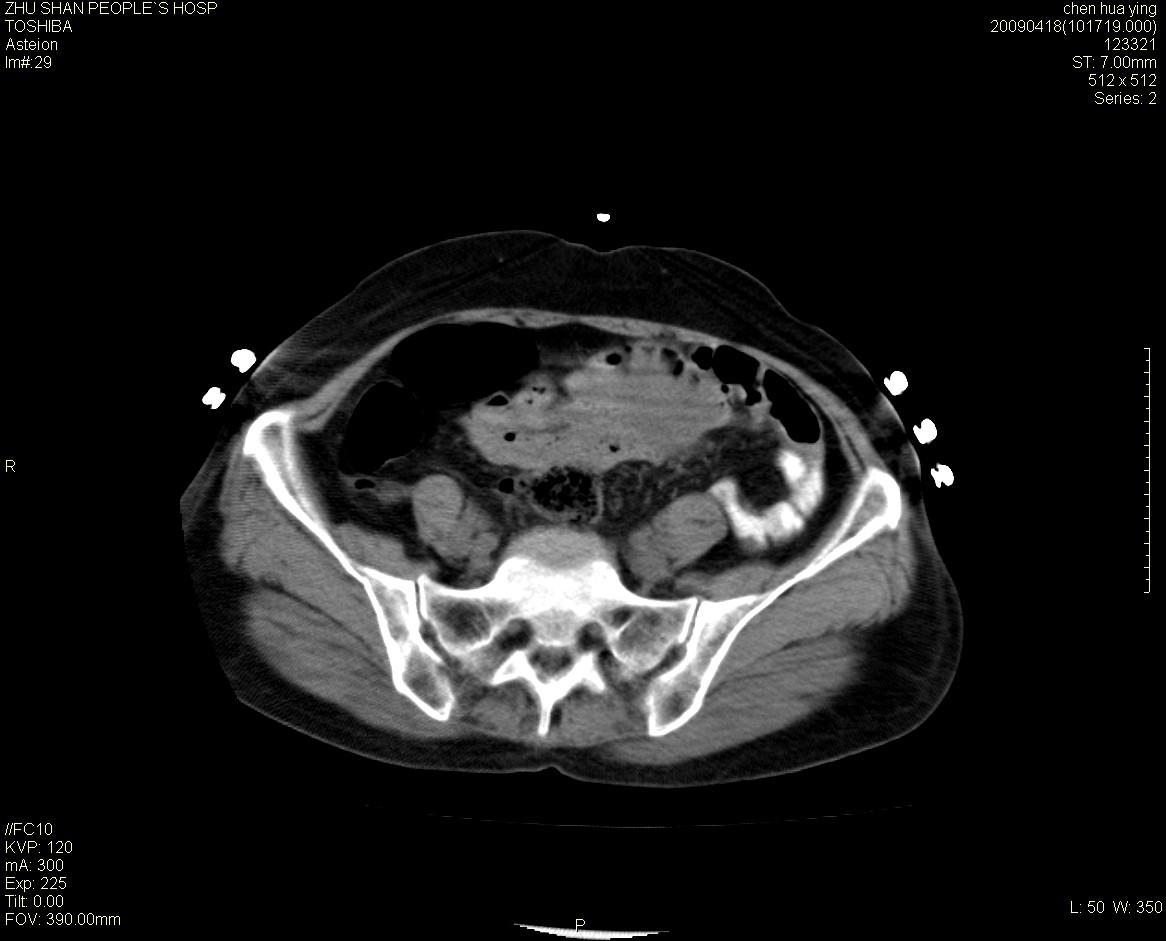

女性病人 65岁 腹部包块半年余结肠造影未见异常.

病灶略呈圆形有分叶状,上部层面呈实性,右侧见圆形低密度区,灶内见团块状钙化,病灶下方与肠管分境不清,考虑间质瘤可能性大,建议肠道准备后增强

病人有腹部手术病史,建议提供临床资料.